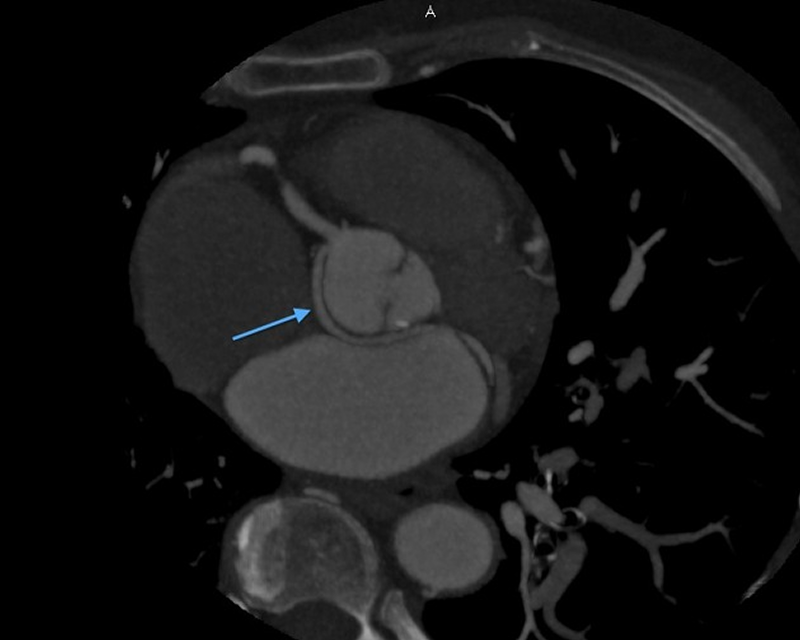

CASE 1- Coronary anomaly- LCX FROM RCA

Anomalous origin of the Left Circumflex artery from Right Coronary artery identified by imaging with Multidetector Computed Tomography

On MDCT angiography, left coronary artery was seen to arise from the left sinus of valsalva which further coursed along the anterior interventricular groove as LAD. RCA was seen to be arising from anterior aortic sinus with its normal course along right atrio-ventricular (AV) groove. There was a vessel seen arising form its proximal segment which took a retro-aortic course towards the left AV groove. It was labelled as LCX as it followed the normal course of the LCX along left AV groove.

Anomalous origins of the coronary artery are rare, but they are of paramount importance for their catastrophic sequelae like myocardial ischemia or even sudden death. MDCT has made it so easy for the detection of such anomalies due to its spatial resolution and 3D image reconstructionThough this anomaly is non-contributory to myocardial ischemia, it seems to be important to identify it as otherwise it would have been misdiagnosed as complete occlusion of LCX which was not the case.